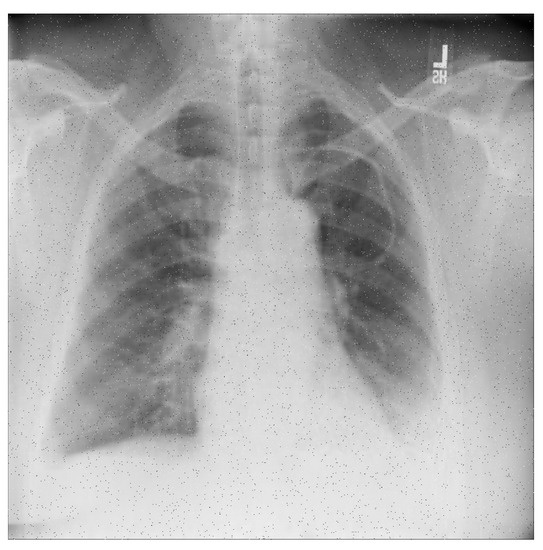

For a more intuitive understanding, we visualize a sample of each category in Figure 9, Figure 10 and Figure 11.

Figure 10. Pneumonia sample: X-ray Image dataset.

Applsci 13 00454 g010